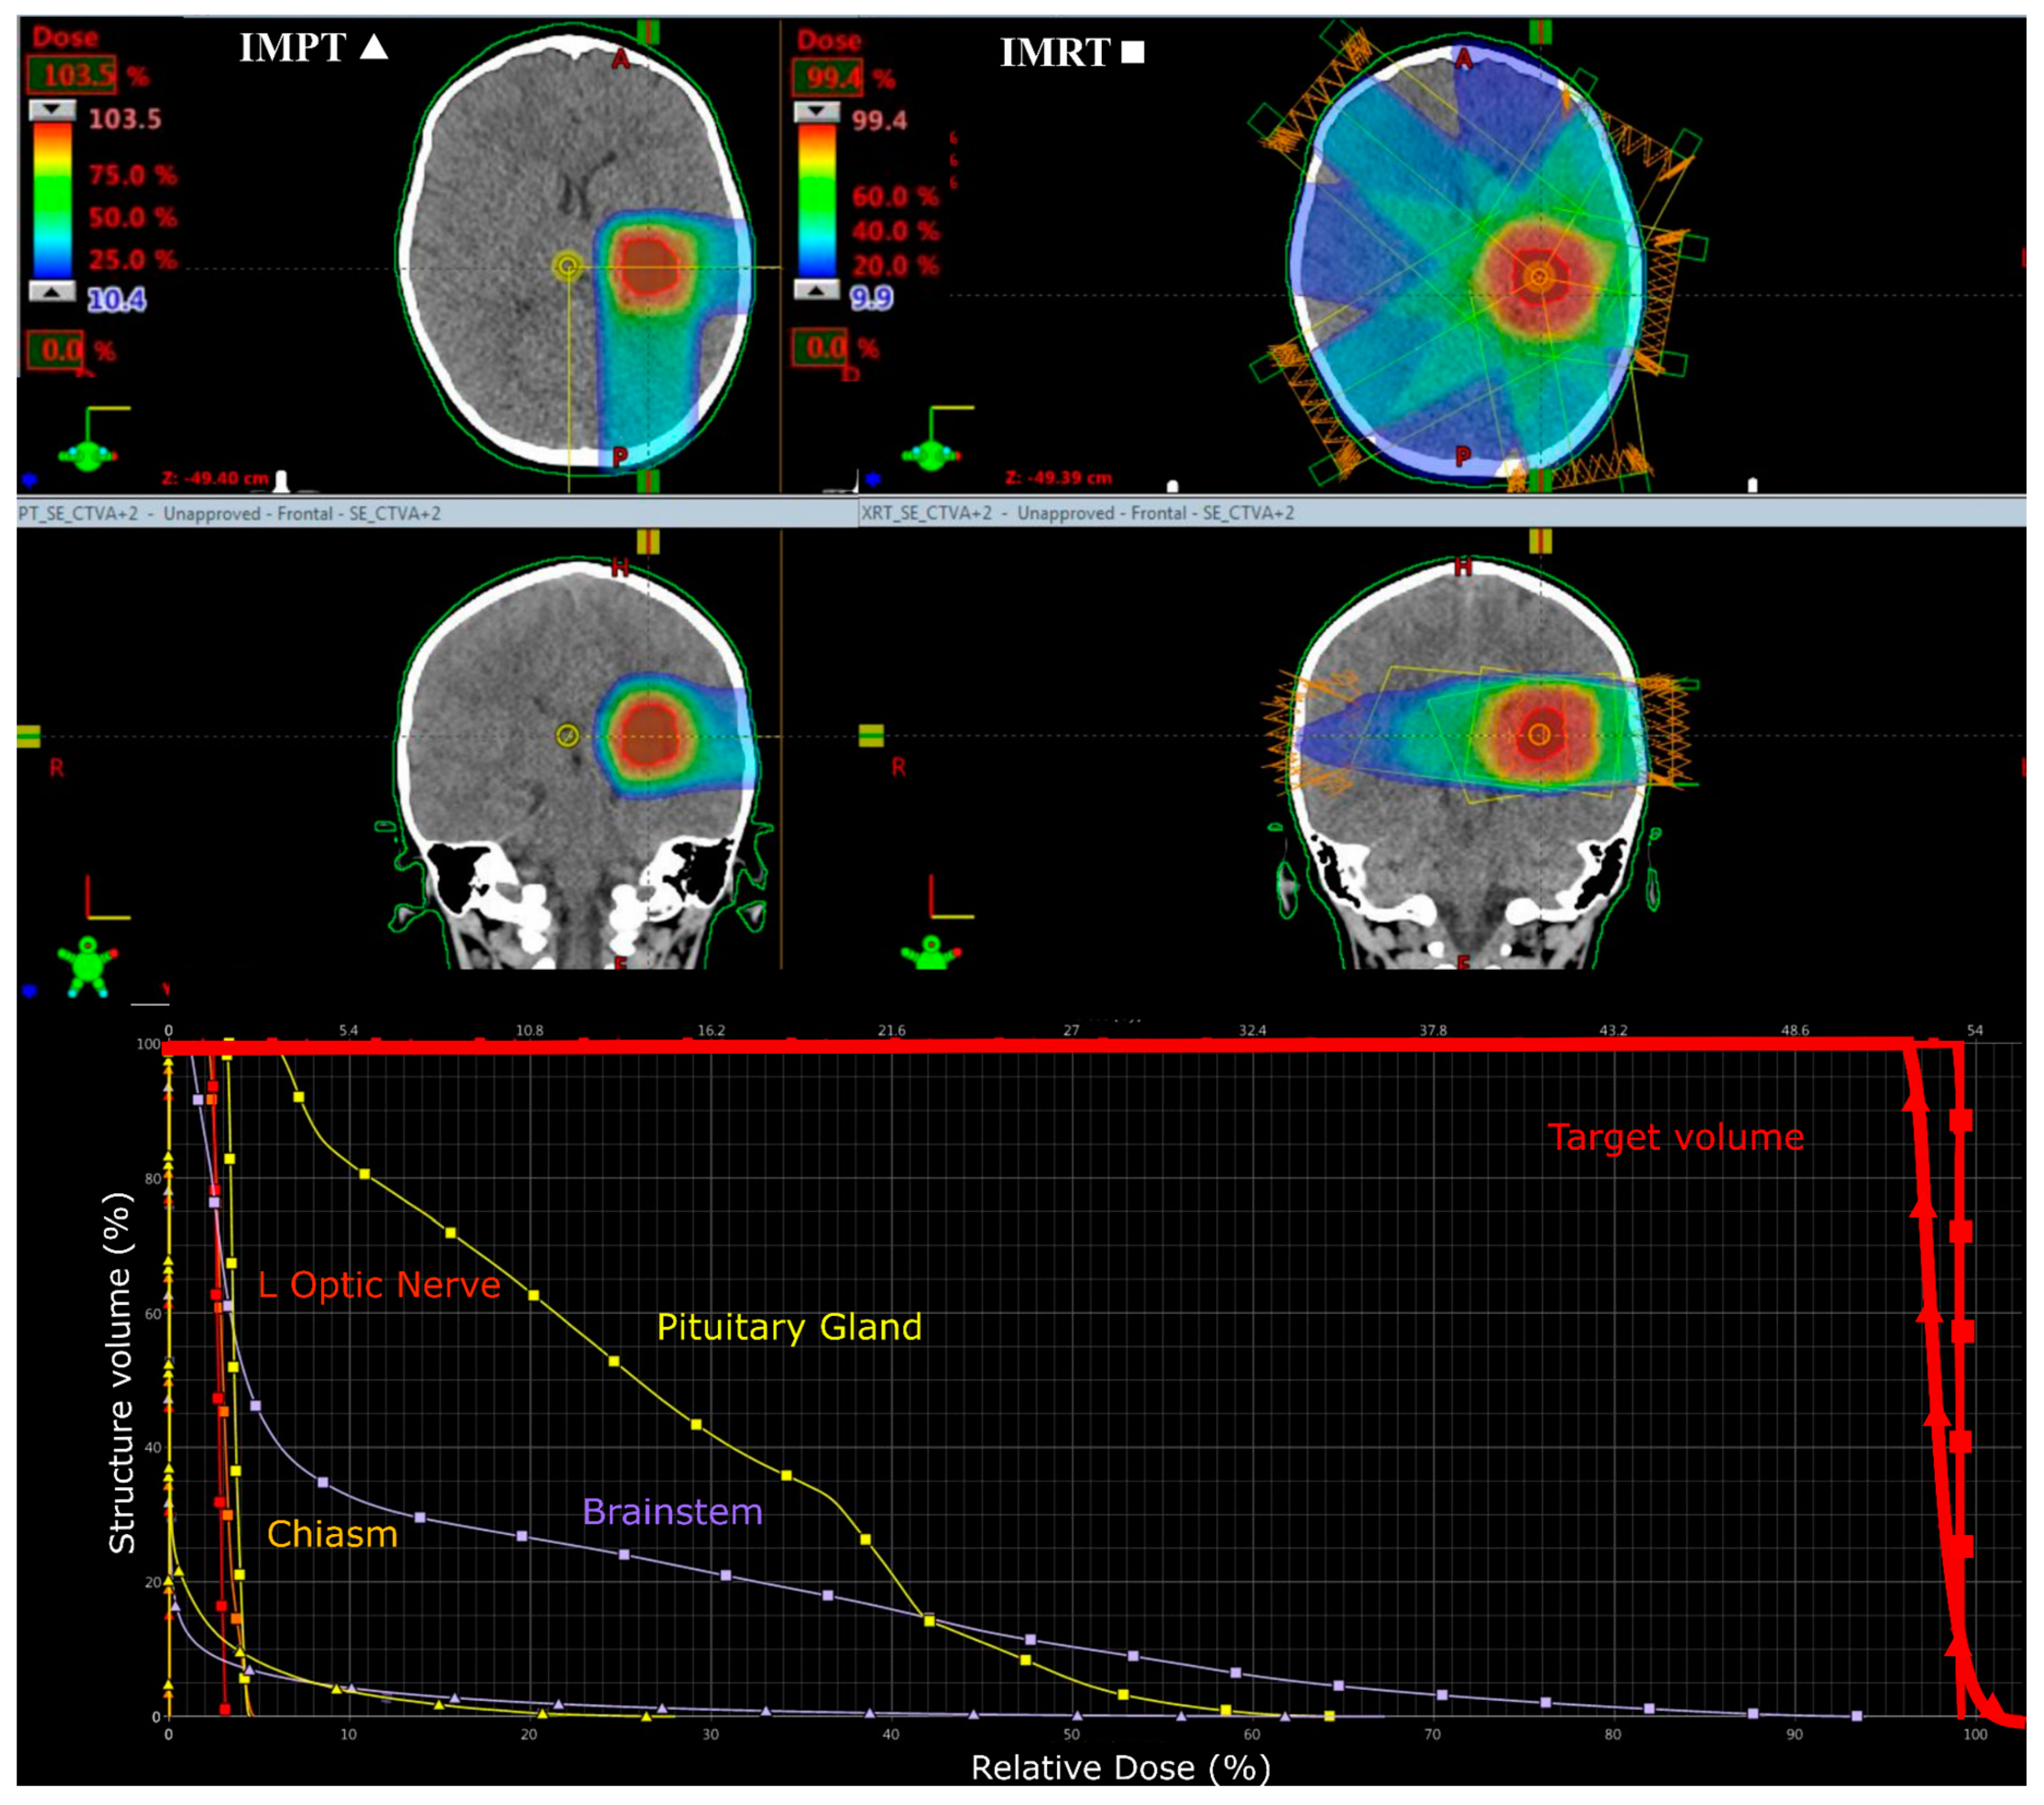

Target volumes achieved ≥95% of the prescribed dose and all OAR were within tolerance levels (Figure 4). There was no significant difference in maximum dose to the CTV averaged across patient plans between modalities (p > 0.05), indicating that all plans yielded the same coverage of the CTV.

Figure 3. Colourwash dose distributions and dose–volume histograms for a 13-year-old male with infratentorial medulloblastoma. Typical planning beam arrangement viewed on axial CT images for IMPT tumour bed (top left) and craniospinal (top right) and IMRT tumour bed (bottom left) and craniospinal (bottom right) plans. Respective dose–volume histograms are shown below.

Figure 4. 13-year-old female with infratentorial medulloblastoma. Typical composite plan showing D95 coverage of the clinical target volume in IMPT (left) and IMRT (right) plans.